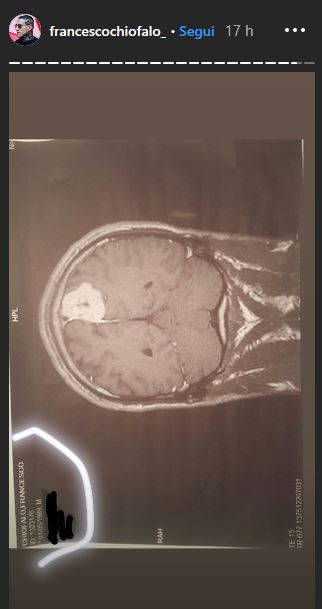

Chiofalo ha scelto di mostrare anche le immagini della massa tumorale che ha in testa, visibile anche a chi non è del mestiere, e ha ammesso che subito dopo le feste si dovrà sottoporre ad un delicato intervento che ha l’80% di non riuscita, con alte probabilità di invalidità permanente. L’ex fidanzato di Selvaggia Roma non ha scelta e si dovrà operare per forza: i medici sono stati molto chiari. Il ragazzo conclude dicendo che in questo periodo sarà assente dai social e che non sa se e quando potrà tornare a mostrarsi in video.